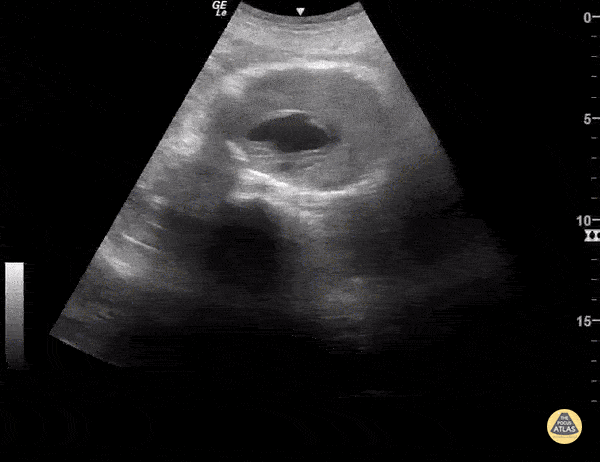

Aorta - Abdominal Aortic Aneurysm

AAA is defined as a localized balloon-like dilatation of the abdominal aorta greater than 3cm. Risk factors include male sex, increased age, and tobacco use. AAAs should be closely monitored for changes in size. Due to the risk of rupture, elective surgery is recommended when the dilatation is greater than 5-5.5cm, or it is growing in size by greater than 1cm/year. The classic triad of a ruptured AAA include pulsatile abdominal mass, hypotension and pain. This AAA has an intramural thrombus. Some studies have claimed that POCUS has a ~100% sensitive for increased diameter. 3cm from outer wall to outer wall defines an aneurysm. Slow, graded compression is key to move the bowel out of the way in any abdominal study. Sukh Singh, MD